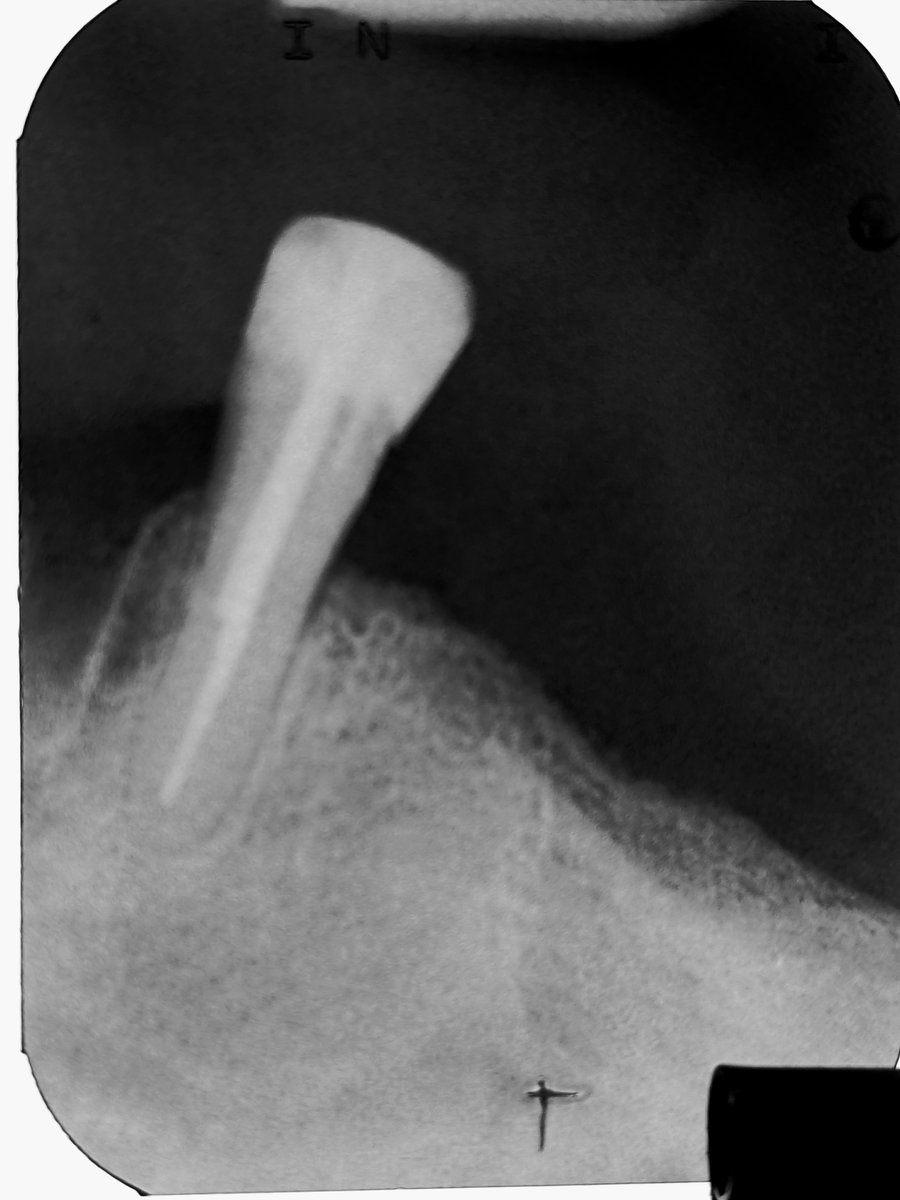

Das Röntgenbild zeigt den Parapost als hellen, parallelwandigen Schatten, der tief im Wurzelkanal verankert ist. Die Länge der Verankerung ist wichtig für die Retention der späteren Krone.